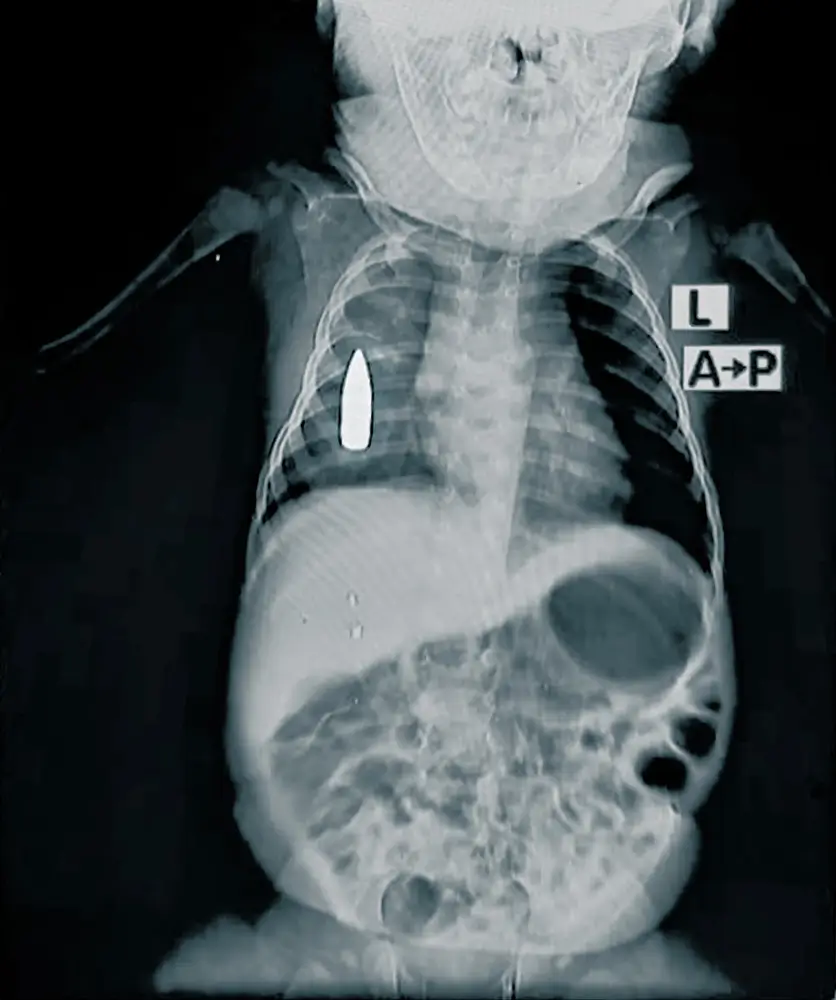

Radiografía de Riyad de 18 meses. Recibió un impacto de bala perdida en el pecho mientras dormía una siesta en Jartum, Sudán. © MSF

“Riyad, un bebé de 18 meses, fue trasladado a urgencias después de que una bala perdida impactara en su costado derecho mientras dormía la siesta en casa de su familia”, explica el Dr. Moeen*, jefe del equipo médico de MSF.

“El equipo médico luchó durante cuatro horas para estabilizarlo. Debido a la gran pérdida de sangre, las probabilidades de que sobreviviera a la operación eran del 50%”.

El equipo pudo detener la hemorragia, pero la bala sigue alojada en su pecho. No está claro cuánto tiempo pasará antes de que se pueda hacer algo al respecto. El hospital no dispone de capacidades quirúrgicas avanzadas, en parte debido al bloqueo sistemático del envío de material quirúrgico desde octubre del año pasado. También es muy complicado derivar pacientes fuera de la zona ya que las rutas de transporte están destruidas o son demasiado peligrosas. Riyad es uno de los 314 niños y niñas tratados por heridas de bala (201 menores) y explosión (113) en 2024.